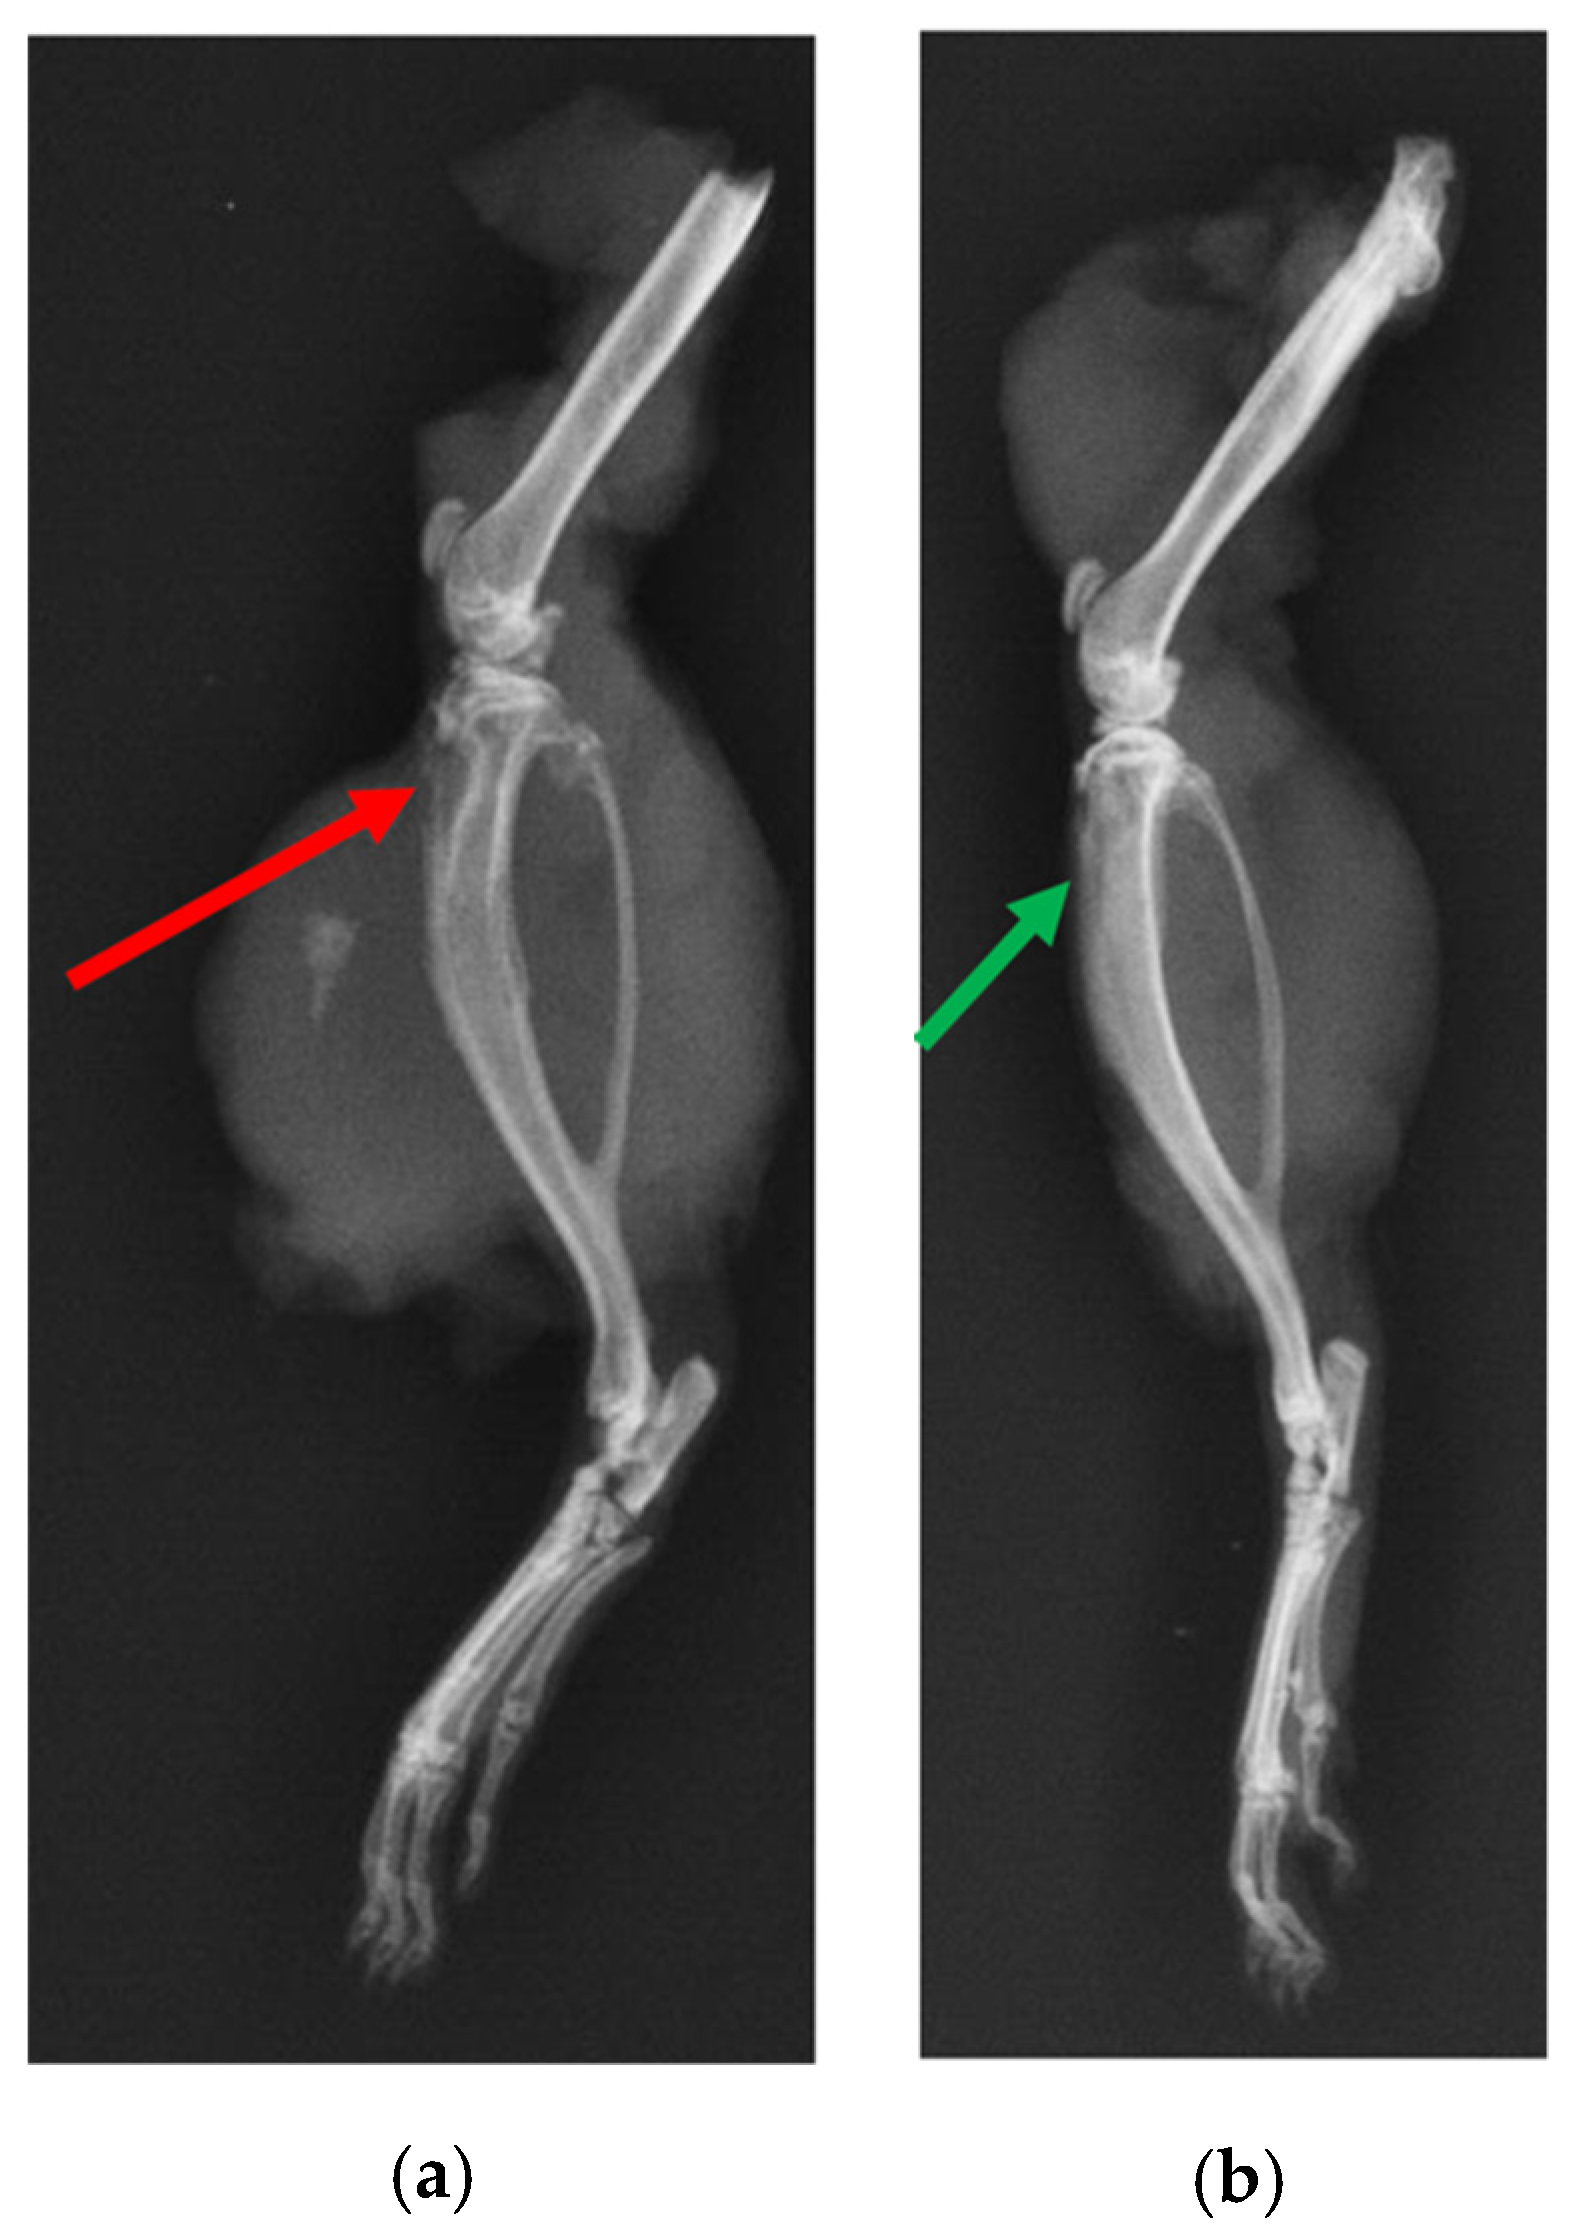

X-ray of the tibia in the infection control group (i.e., BG containing putty with no antibiotic) showed classic signs of infection such as un-healed, osteolytic, and deformed bone (Figure 10). A narrowing of marrow space was also visible. In contrast, the tibia of the treatment group (ABVF-BG putty with vancomycin) showed no signs of infection, and the bone appeared to have healed (Figure 10). μ-CT images showed the presence of infection in the control rat tibia (Figure 11a), including signs of osteomyelitis such as narrowing of the marrow space, the presence of a puss-filled fibrous capsule, sinus tracts, and deformed bone with ectopic bone growth. Alternatively, healing bone without signs of infection was seen in the μ-CT images of tibia from the treatment rats. Specifically, the drilled hole at the surgical site was being filled by immature cancellous and cortical bone (Figure 11b).

Figure 10.

X-ray of rat tibia. (a) The red arrow indicates osteomyelitic bone in the control rat. (b) Alternatively, the green arrow shows healed bone in the treatment group.

In spite of the conundrum surrounding our cytotoxicity assay, the in vitro studies indicated the overall safety and efficacy of our ABVF-BG putty; hence, we proceeded to assess our ABVF-BG putty in vivo, with promising results. X-ray imaging showed healed or healing bone in the treatment group (Figure 10b). In contrast, the infection control group showed the telltale signs of osteomyelitis: deformed bone, osteolysis, periosteal thickening, and formation of sequestrum (Figure 10a). The μ-CT of the bones confirmed the findings. The treatment group bone showed no signs of osteomyelitis, as the bone appeared to be healed with new bone formation and remodeling taking place (Figure 11b). On the contrary, severe osteomyelitis was seen in the infection control group with decreased and deformed bone formation, narrowing marrow space, and the formation of sinus tracts. Infection seemed to be spread to the posterior of the bone, and the presence of a puss-filled capsule was also seen (Figure 11a).